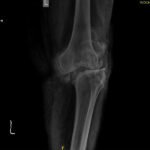

- Partial Knee replacement: If there is arthritis involving only one compartment out of the three in the knee, than we can do half knee replacement. Usually it is the inner side of the knee which is affected in early stages.

In advanced stages of arthritis patient experiences pain on movement, disturbed sleep, stiffness, swelling and deformity. Sometimes pt needs walking stick and not relieved by non surgical treatment than total knee replacement is the operation of choice.

In this the arthritic and eroded joint surface is removed and replaced with an artificial knee prosthesis made of specialized metal and high grade plastic. The operation also corrects the deformity if present.